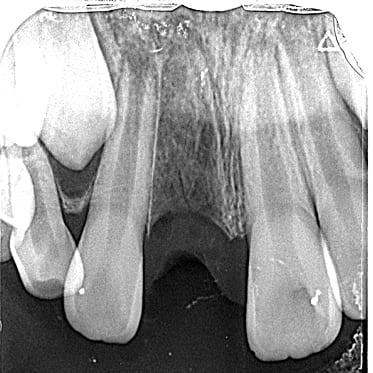

01 左下7の近心根にエンジンファイルの破折

02 ファイル除去時

※根尖周囲の透過像はまだ残存

03 最終の根充剤を充填

※根尖透過像が小さく治癒方向へ向かっている